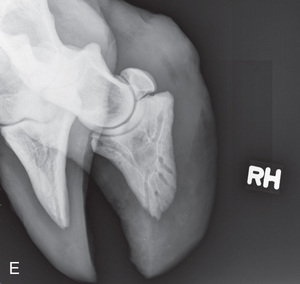

Shoulder Optional views | Mediolateral (ML) | Lateral (L) |

To attain quality projections of the shoulder joint, the use of general anesthesia and placement of the patient in lateral recumbency are recommended. The standing position may be possible if the patient tolerates manipulation. The easiest and maybe only view of the shoulder that can be obtained is the mediolateral.